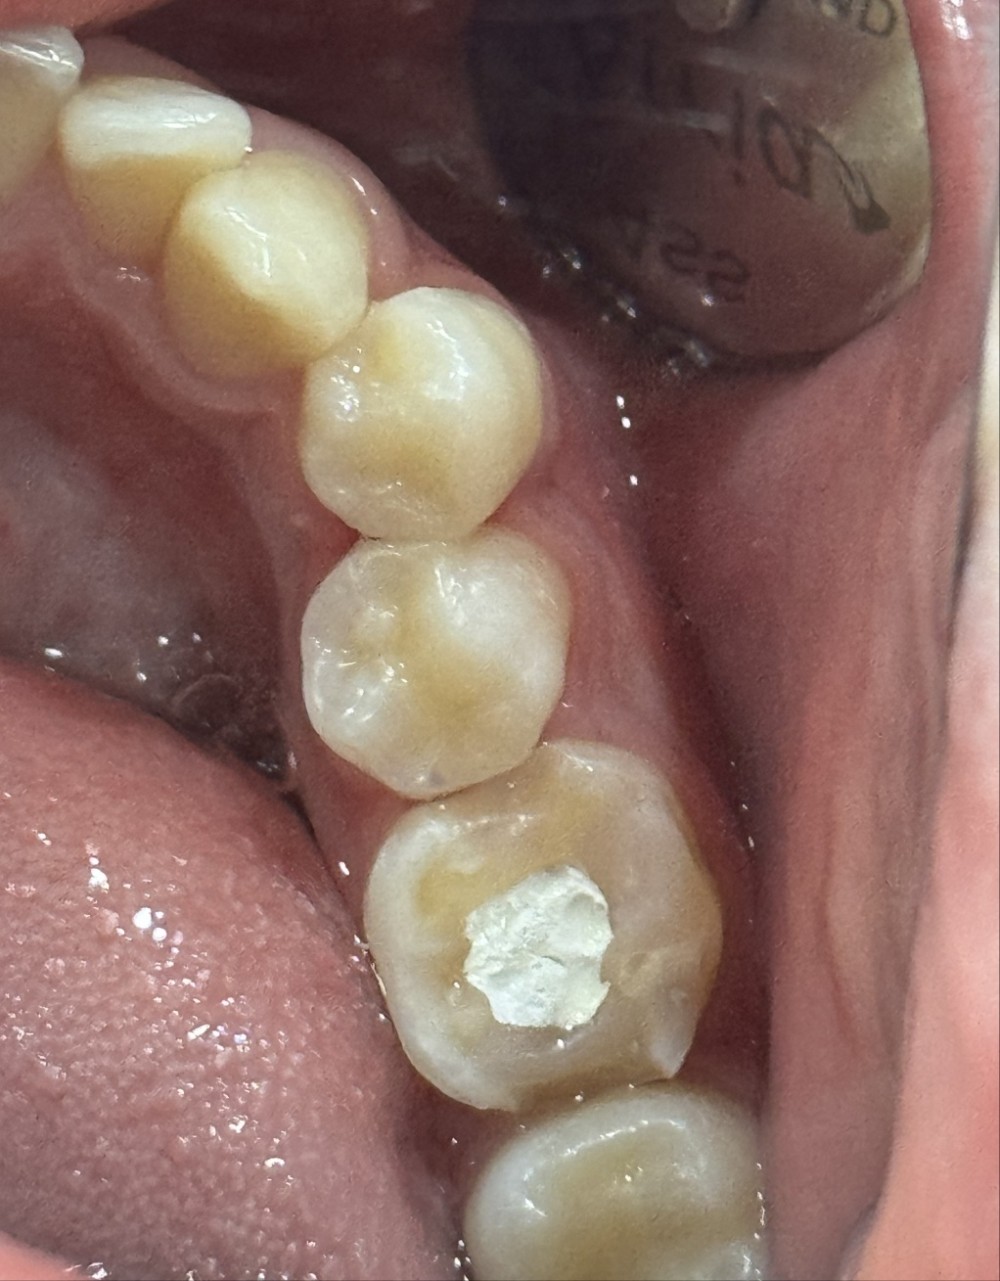

퀴즈! 이맥스 인레이치료한 치아를 찾아주세요

힌트 : 2개

답: 작은어금니 2개

이맥스는 심미적 장점, 치아와 비슷한 강도, 뛰어난 접착력 흠잡을데 없는 재료입니다.